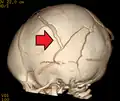

An intraparenchymal bleed with overlying skull fracture from shaken baby syndrome